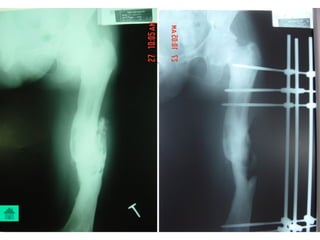

Baát ñoäng xöông

Coá ñònh ngoaøi:

 Coáñònhngoaøilaøphöôngphaùptieâuchuaåntrongvieâmxöông

khôùpgiaû.

- Theo ñuùng nguyeân taéc coá ñònh ngoaøi

- Giöõ trong moät thôøi gian daøi, coù theå moät naêm hoaëc hôn.

- Thayñinh neáu bònhieãm truøng chaânñinh

- Hai loaïi CÑN löïachoïn laø Ilizarov vaø khung ñôn giaûnduøng ñinh Chanz .

Ñinh, neïp:

 Nguy cô nhieãm truøng cao, nhöng moät soá

tröôøng hôïp cuõng duøng.